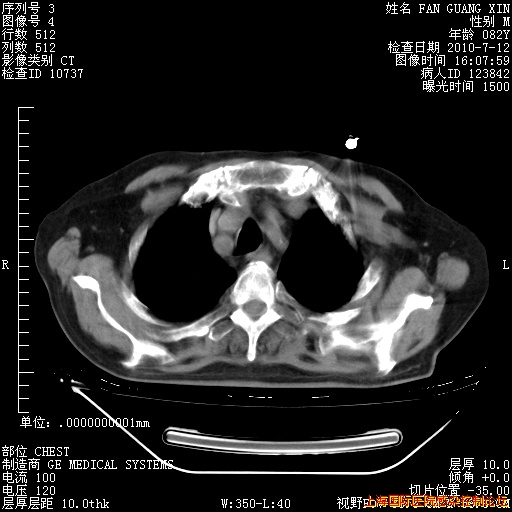

6月12日纵膈窗